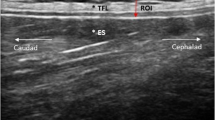

Briefly, the participants sat on a treatment table, bending the trunk until the examiner determined an approximate flexion angle of 60 degrees (starting position), and here, a static US image was taken (Philips Lumify linear transducer L12-4, 12 MHz; Philips Ultrasound Inc., Bothell, WA; Fig. 1A, B). Participants then extended the trunk to 0 degrees, which was the ending position of the trunk extension task (TET), and again, a static, second US image was taken (Fig. 1)C, D). The distance between the junction of the latissimus dorsi muscle and the TLF and an artificial reference made by a reflective tape on the skin shown in the images was measured (Fig. 1B, D). The difference between the distances of the starting position and the ending position represent the extent of the TLFD (Fig. 1B, D).

Measurement procedure. (A) Flexion phase trunk extension task. (B) Measurement time point t1. (C) Fully extended position of trunk extension task. (D) Measurement time point t2. The left white cross on the measurement line marks the LD/TLF junction. The white cross on the right marks the center of the artificial reference created by a reflective tape on the skin. TLF, thoracolumbar fascia; LD, latissimus dorsi muscle.